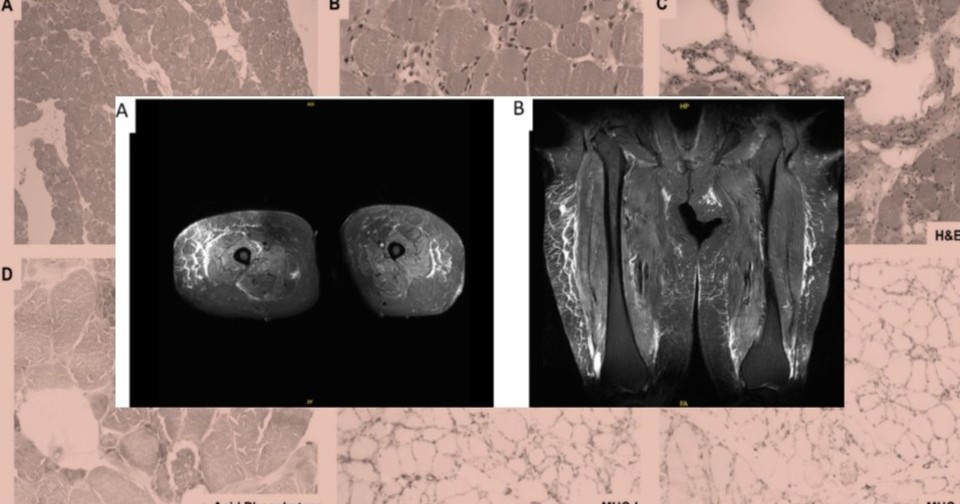

Физикальное обследование выявило повышение температуры тела, значительную слабость в проксимальных группах мышц. Исключив другую этиологию миопатии, врачи провели анализ на специфические антитела и подтвердили диагноз иммуноопосредованной некротизирующей миопатии и связали ее развитие с приемом семаглутида. При биопсии мышц бедра обнаружились рассеянные некротические и регенерирующие мышечные волокна, а иммуногистохимические исследования выявили наличие макрофагов с миофагоцитозом. На некротизированных миофибриллах также наблюдалось положительное окрашивание мембраноатакующего комплекса.